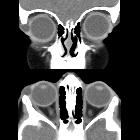

Dermoidzyste der Orbita

Radiographic features

These lesions are usually extraconal, non-enhancing masses with smooth margins, cystic and/or solid components. They are typically heterogeneous with soft tissue, fluid and fatty (sebum) components; occasionally calcifications may be present.